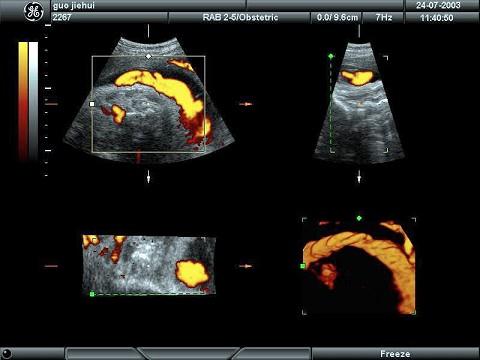

某孕妇胎儿颈部可探及下列图像,最可能的诊断为?(?)A.脐带绕颈B.胎盘早剥C.先天畸形D.正常结构E.脐带搭颈

问题 某孕妇胎儿颈部可探及下列图像,最可能的诊断为?(?)

选项 A.脐带绕颈 B.胎盘早剥 C.先天畸形 D.正常结构 E.脐带搭颈

答案 A